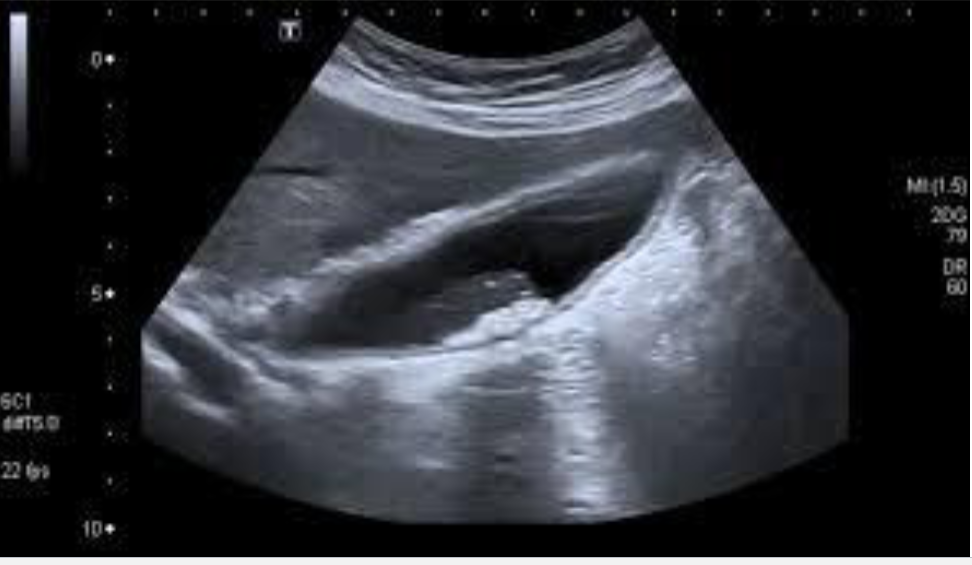

US—distended GB & cystic duct w/ stones, thickened wall, sonographic Murphy’s, pericholecystic fluid

Acute Cholecystitis

Thickened wall, double wall sign, sludge & stones with acoustic shadowing